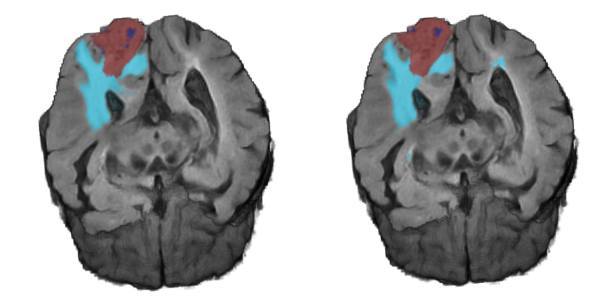

Brain lesion segmentation is a critical application of computer vision to the biomedical image analysis. The difficulty is derived from the great variance between instances, and the high computational cost of processing three dimensional data. We introduce a neural network for brain tumor semantic segmentation that parses their internal structures and is capable of processing volumetric data from multiple MRI modalities simultaneously. As a result, the method is able to learn from small training datasets. We develop an architecture that has four parallel pathways with residual connections. It receives patches from images with different spatial resolutions and analyzes them independently. The results are then combined using fully-connected layers to obtain a semantic segmentation of the brain tumor. We evaluated our method using the 2017 BraTS Challenge dataset, reaching average dice coefficients of 89% , 88% and 86% over the training, validation and test images, respectively.